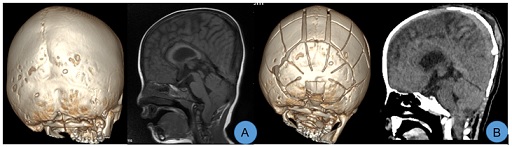

Compared to PVDO, PCVR involves extensive detachment of the skull from the dura mater surface, posing risks of damaging the dura mater and venous sinuses. This method has disadvantages including significant surgical trauma, prolonged operation times, and excessive intraoperative bleeding [29]. Some scholars recommend preoperative 3D CT venography or MRV to identify the position of the venous sinuses and exclude the presence of variant occipital sinuses, thereby reducing the risk of intraoperative venous sinus injury [30]. In this cohort, three cases underwent extensive posterior cranial fossa bone flap dissociation. Despite high intracranial pressure causing uneven compression and adhesion of the skull to the dura mater, careful dissociation prevented venous sinus injuries (Figure 4). For children with higher intracranial pressure, floating bone flaps without dura mater dissection may be employed to prevent venous sinus injury. However, such flaps can only expand passively through brain tissue expansion, and the postoperative shaping effect is suboptimal, significantly influenced by body position, with a high probability of postoperative recurrence. When performing floating bone flaps, absorbable connecting pieces can be used to fix and elevate the flaps above the torcular herophili, or fence-shaped incisions can be made on surrounding bone flaps to induce greenstick fractures and improve outcomes. Although PVDO can increase cranial cavity volume more significantly than PCVR, deformities like parieto-occipital stenosis, mere anterior-posterior expansion may not yield satisfactory cranial appearance, and lateral shaping should be considered. PCVR not only increases the anteroposterior diameter of the skull but also alleviate parieto-occipital stenosis, reduce skull height, and improve oxycephaly. Both the postoperative cranial index and the asymmetry index of plagiocephaly have shown significant improvements [31]. PVDO with higher rates of infection when compared PCVR due to the exposure of distractors. Especially for patients with hydrocephalus who have undergone ventricular shunting, PVDO will increase shunt failure and infection that usually need for additional intervention [32]. Additionally, distraction surgery poses risks of device fracture and requires regular adjustment of the traction device along with a secondary surgery to remove the extender, leading to a prolonged treatment cycle. Reports suggest that the incidence of postoperative complications, such as surgical incision infection and device fracture, can be as high as 32.2% following distraction surgery, which is higher than that following posterior cranial fossa remodeling (5% - 11%) [33]. Among the seven children in this study, there were no cases of venous sinus or dura mater injury, cerebrospinal fluid leakage, or postoperative infections, indicating that PCVR is relatively safe and the risks are manageable.

Figure 4: Due to the high intracranial pressure, the brain tissue is significantly compressed, and the skull appears uneven.